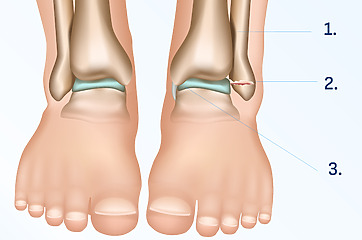

Broken Ankle – What is Weber Classification?

Patients often ask about Weber classification if they want to better understand their injury. This is used to assess the severity of the ankle fracture and how much the ankle has moved from its original location. It focuses on exactly where it is in relation to the syndesmosis – which is the articulation between two bones in the lower limb.

Ankle fractures according to the Weber classification are divided into three categories, depending on where they are located:

Type A: located below the syndesmosis.

Type B: passes through the syndesmosis.

Type C: located above the syndesmosis.

These three types of fractures can have different consequences and require different treatments. For example, a type C fracture may be the most severe because it may be associated with joint injury and require surgery.[23]